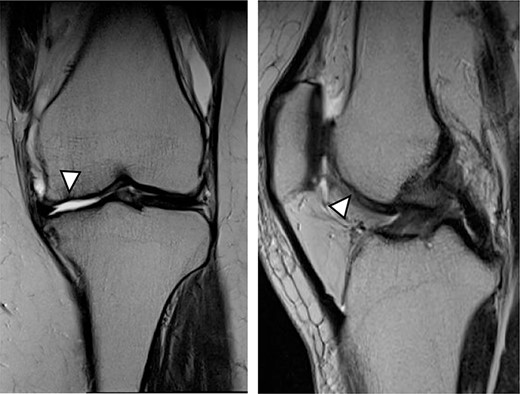

MRI showed cartilage injury of the medial femoral condyle (arrowhead).

As a control case, a 51-year-old female (BMI, 24.1 kg/m2) presented with 4.5 years of left knee medial joint pain. Preoperative Tegner scores, Lysholm scores and KOOS scores are shown in Table 1. Preoperative radiographs of the left knee joint showed mild medial osteoarthritis (OA) of the knee and hip–knee–ankle (HKA) angle of 1.3-degree varus. MRI showed cartilage injury at the MFC (Fig. 6). Approximately 0.5 g of the healthy cartilage was harvested from less weight-bearing regions of the intercondylar notch using arthroscopy. The specimen was sent to J-TEC for cartilage culture. At 4 weeks after the harvest, the microfracture was performed at a 4-mm power pick at the cartilage lesion, and the two-stage implantation of tissue-engineered cartilage-like tissue (JACC) was performed on the cartilage injury site (4.5 × 5.5 cm; Outerbridge classification, Grade III), and then the tissue implantation site was covered with periosteum taken from the tibia of the same patient (Fig. 7). Knee joints were immobilized for 4 weeks with a soft knee brace. A ROM exercise is started with a continuous passive motion device at 3 weeks after surgery. Partial weight-bearing (30% body weight) was allowed at 4 weeks, and full weight-bearing permission was given from 8 weeks after the surgery.

MRI findings at 1 year after the surgery indicated signal intensity area in the grafted area for the patient with JACC (Fig. 8), whereas the patient who underwent Reveille CP exhibited greater thickness at the grafted area as compared to the surrounding healthy cartilage (Fig. 9). The MOCART score at 1 year after the Reveille CP surgery (60 points) was higher than that of JACC (50 points).

One year after JACC, MRI showed T2 high intensity area in the graft area (arrowhead).